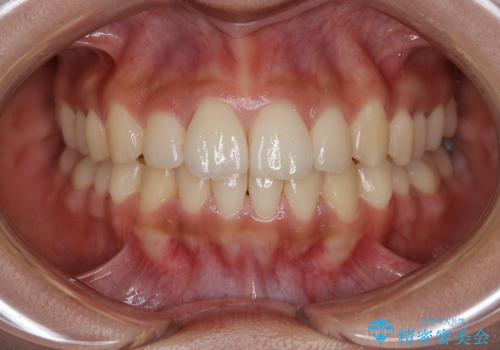

[ 非抜歯矯正 ] 歯を抜かずに出っ歯の治療

![[ 非抜歯矯正 ] 歯を抜かずに出っ歯の治療の症例 治療前](https://seimitsushinbi.jp/wp/wp-content/uploads/2025/03/IMG_6660-500x350.jpg?v=1741945892)